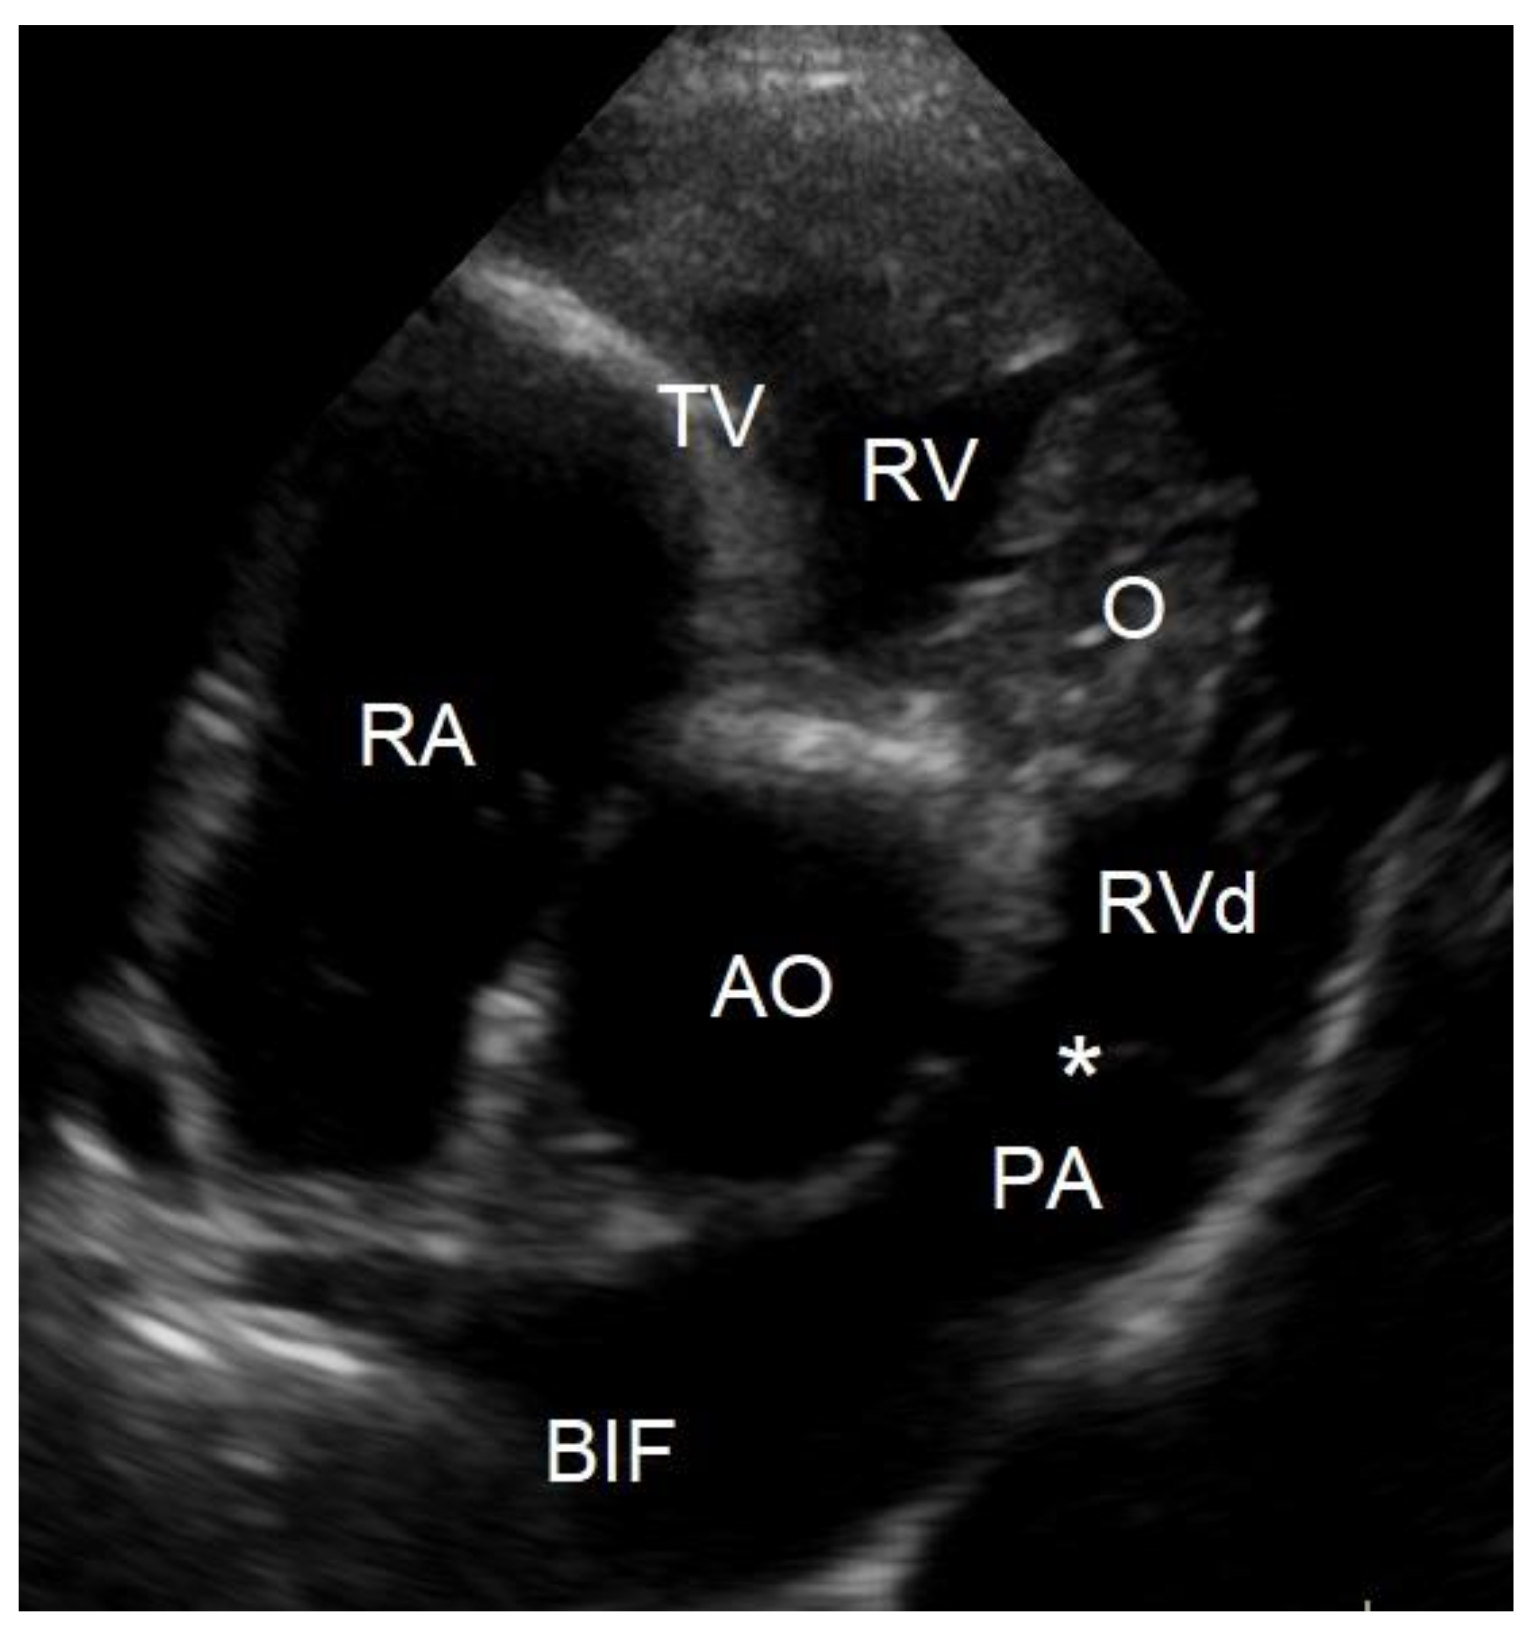

To evaluate the cause of the murmur and the cause of the dyspnea after having obtained thoracic radiographs, an echocardiography was performed in an awake dog without sedation. Echocardiography showed a severe localized right ventricular concentric hypertrophy and a severe obstruction of the right ventricular outflow tract caused by a localized muscular hypertrophy within the right ventricle (Figure 3). The right ventricular lumen at the level of the obstruction measured 1.2 mm, and continuous wave Doppler interrogation revealed a pressure gradient of at least 88 mmHg between the proximal high-pressure and the distal normal-pressure right ventricular compartments. The pulmonary artery and pulmonary valve looked normal, with an annulus diameter of 8 mm and with a normal peak flow velocity of 1.1 m/s (Figure 3). There was no tricuspid valve regurgitation present. The right atrium was subjectively mildly dilated. The left ventricle and left atrium were underfilled (Figure 4). There was a trivial aortic valve regurgitation present, probably secondary to the VSD, since the aortic valve leaflets looked normal. The aortic root diameter was 10 mm. Just underneath the aortic valve, a VSD was seen with a diameter of about 2.5 mm, and color Doppler revealed right-to-left shunting from the high-pressure compartment of the right ventricle to the left ventricle with a pressure gradient of 13 mmHg. A bubble study, i.e., injection of agitated physiologic saline solution intravenously, confirmed the right-to-left shunting at the level of the ventricles (Figure 5). There were no ascites or hepatic venous congestion present.

Figure 3. Two-dimensional cross-sectional echocardiographic image at the level of the heart base from the standard right parasternal short axis view at 3 years of age shows a localized muscular hypertrophy in the right ventricle (O). This obstructive muscular lesion resulted in a severe concentric hypertrophy of the right ventricular chamber proximal to the obstruction (RV) as evidenced by a thick wall, compared to the right ventricular chamber distal to the obstruction (RVd), which has a normal wall thickness. AO—aorta, PA—pulmonary artery trunk, *—pulmonic valve, RA—right atrium, TV—tricuspid valve, BIF—pulmonary artery bifurcation.